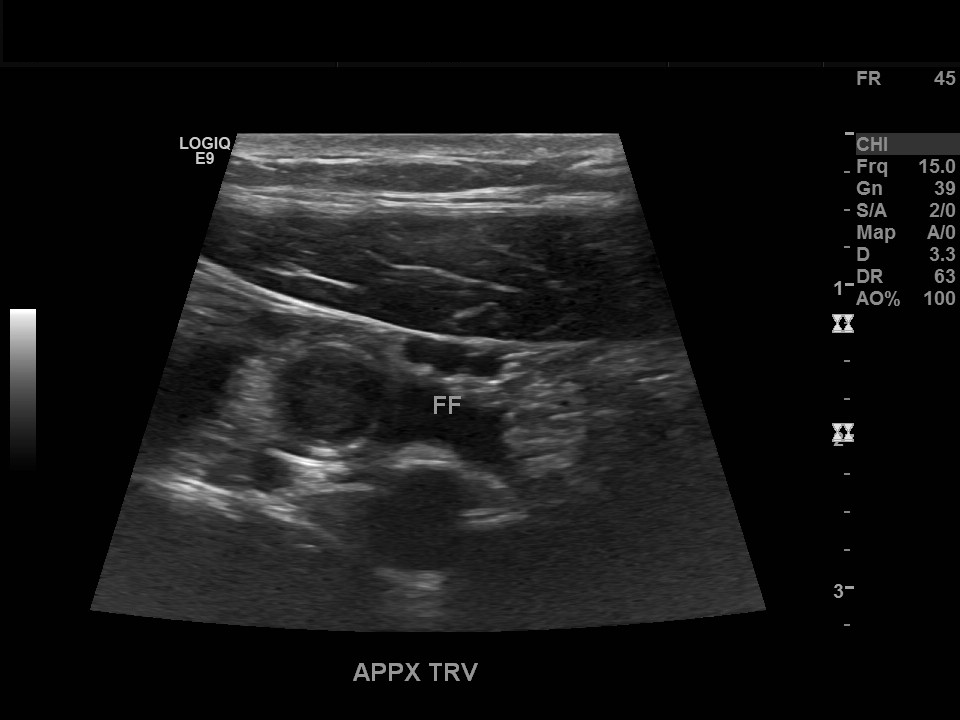

Appendicitis 3

0.9 cm appendicitis curled on itself with, fat stranding trace free fluid.